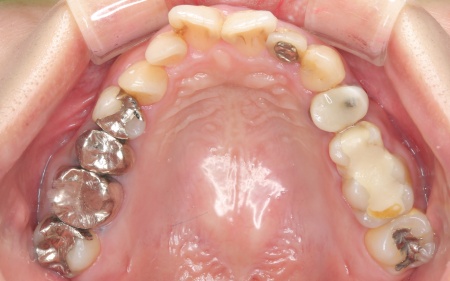

20代女性 ワイヤー矯正で歯並びを整えて虫歯治療やインプラント治療で口腔内全体を改善した症例

詳しく拝見したところ、下の前歯4本を除くほぼすべての歯に虫歯が認められました。 また、左上奥歯1本と左下奥歯1本が欠損しており、その影響で噛み合わせのバランスが崩れているため、噛んだときの痛みにつながっていると考えられます。 このまま放置すると、虫歯が進行したり、欠損部周囲の歯が動いて噛み合わせがさらに不安定になったりするリスクがあるため、虫歯を含めた口腔内全体の治療が必要だと診断しました。 |

治療前